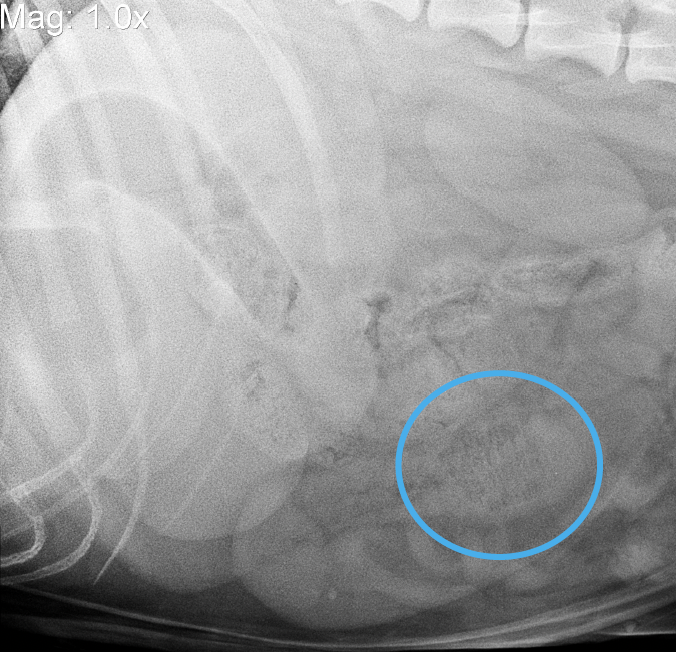

27

Cas 5: * Corgi * Mâle castré, 6 ans * Difficulté à respirer Pourquoi ne voit-on pas complètement le coeur? A. Effet de silhouette secondaire à une opacité de TM dans le lobe crânial gauche B. Déformation et dilatation d’une chambre cardiaque C. Effet de silhouette découlant d’une quantité importante de gras dans le thorax crânial gauche D. Il y a une couverture par dessus le chien pendant la prise de radio

A. Effet de silhouette secondaire à une opacité de TM dans le lobe crânial gauche Erreur de perception visuelle: silhouette créé par du tissu mou anormal dans le lobe crânial G (hémorragie)